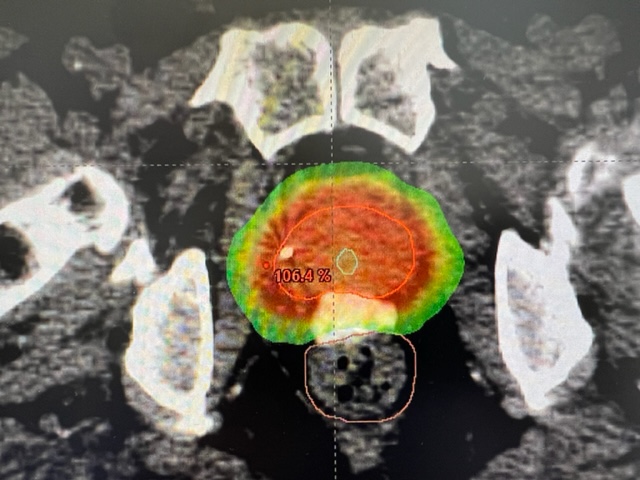

Mapping / CT-Simulation / Computer Planning

Before radiation therapy can start we must perform a CT-simulation. We construct a vacuum-cushion that will hold you still during treatment, then a CT scan of the pelvis is done. No contrast is required. A few marks are placed on the skin. For the simulation and for the treatment we will advise the patient to consume 2 cups of water 30 minutes prior in order to have a comfortably full bladder. If possible the rectum should be empty-ish from a bowel movement earlier in the day. A simulation appointment takes about 30 minutes. Sometimes an MRI scan of the pelvis will also be performed on the same day as the simulation. Next we design a treatment plan on the computer. This does not require any participation from you! It takes 2 – 7 days to create and QA test a computer plan, then we are ready to start treatment on you.